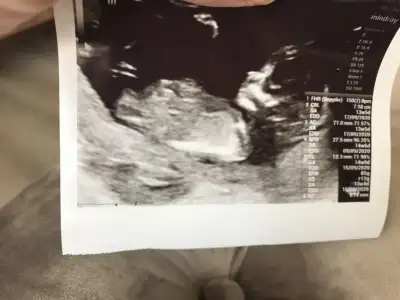

Sevgili @ıkrameyra cinsiyet tahmini alabilir miyim 🌹💕

BDA5C7BD-3496-4BB1-A970-938708FDFC4E.jpeg

Eklentiler

• 61A9F4EF-9683-43B4-B5BD-00CCB355CF56.webp

61A9F4EF-9683-43B4-B5BD-00CCB355CF56.webp

28,5 KB · Görüntüleme: 40

• C8D7EF01-26BB-4FC3-99CF-7FA7C7BDCC8C.webp

C8D7EF01-26BB-4FC3-99CF-7FA7C7BDCC8C.webp

37,8 KB · Görüntüleme: 49